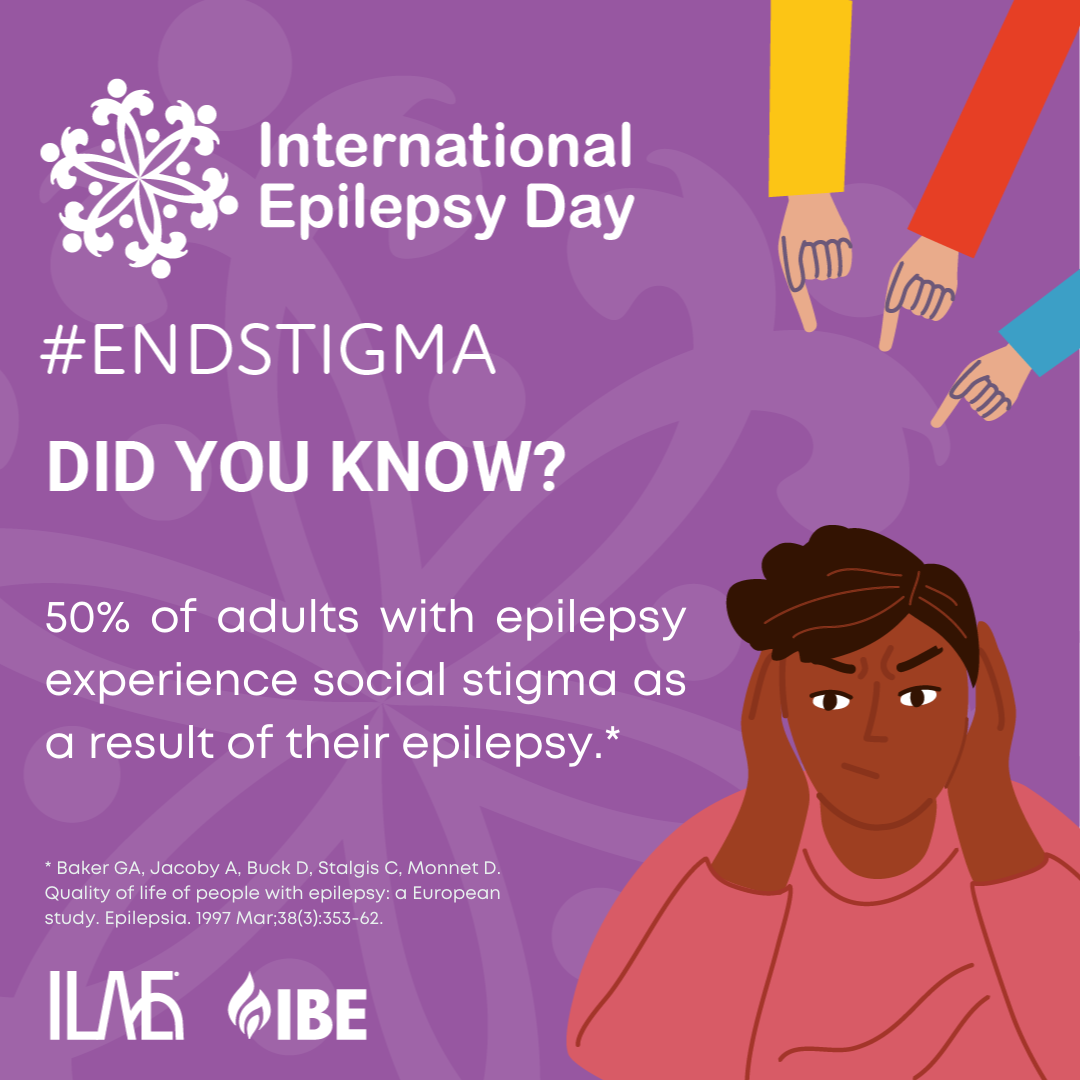

Fighting Epilepsy Stigma On International Epilepsy Day 2023 Novum Law